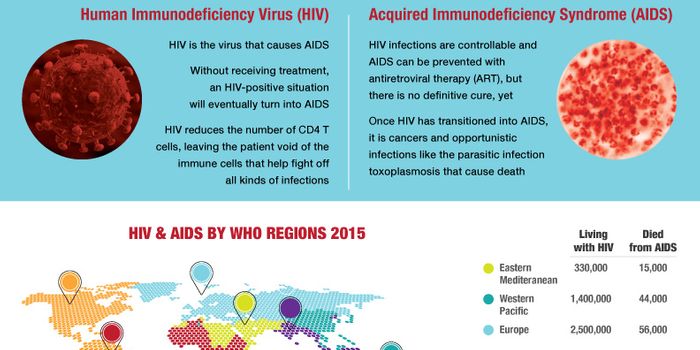

DEC 02, 2014VideosA new study led by the University of Oxford has found that HIV is taking longer to progress to AIDS as it becomes " ...

NOV 28, 2018Health & MedicineDecember 1 marks the 30th anniversary of World AIDS Day. Acquired immunodeficiency syndrome (AIDS) is a chronic, potenti ...